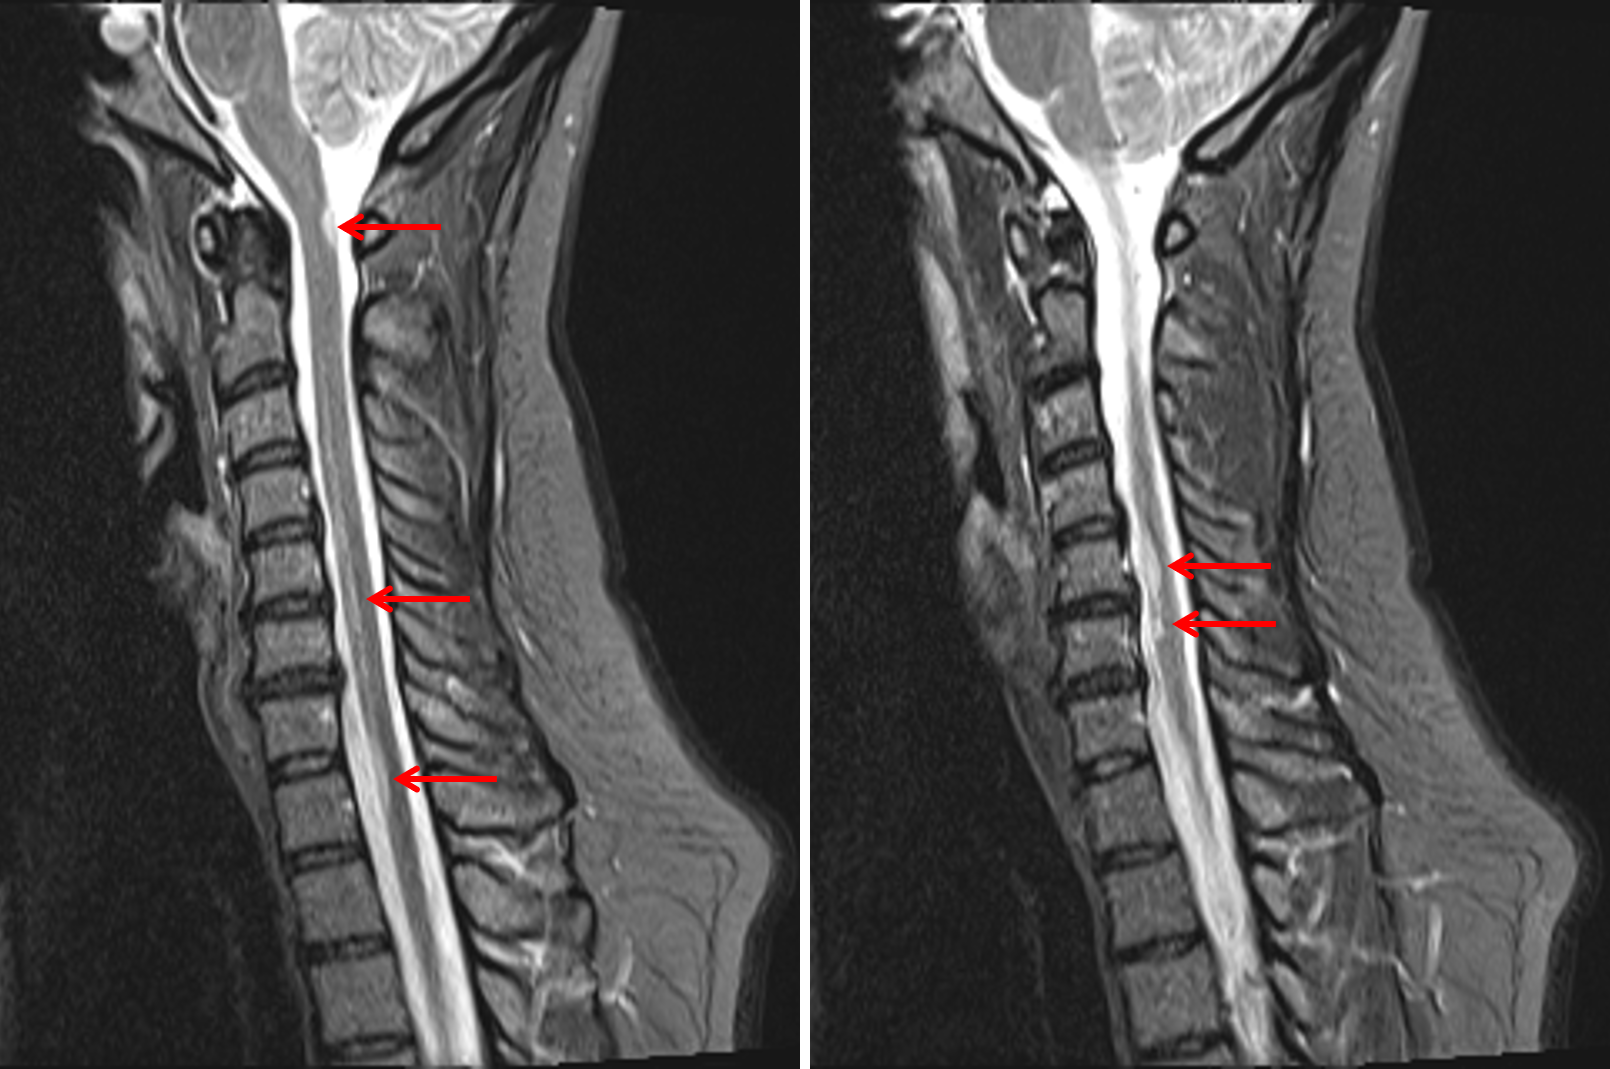

Apr 08, 2021 · this test, also known as magnetic resonance imaging, uses a magnet, radio waves and a computer to create an image of the brain and spinal cord. X trustworthy source national health service (uk) public healthcare system of the uk go to source this test can be helpful in making a multiple sclerosis diagnosis because it often shows abnormalities. An mri looks for evidence of lesions (areas of damage) in the brain or spinal cord that indicate multiple sclerosis. Oct 10, 2019 · multiple sclerosis (ms) is an autoimmune disease that deteriorates the cover that protects the nerves (myelin sheath). Multiple sclerosis can cause a variety of symptoms:

Oct 10, 2019 · multiple sclerosis (ms) is an autoimmune disease that deteriorates the cover that protects the nerves (myelin sheath). X trustworthy source national health service (uk) public healthcare system of the uk go to source this test can be helpful in making a multiple sclerosis diagnosis because it often shows abnormalities. Other symptoms of ms are tingling sensations, constipation, constant fatigue, painful muscle spasms, and hearing loss. This can lead to a wide range of symptoms throughout the body. In ms, the immune system attacks the protective sheath (myelin) that covers nerve fibers and causes communication problems between your brain and the rest of your body. Characteristic areas of demyelination will show up as lesions on an mri scan. Problems in speech (dysarthria) or swallowing (dysphagia), visual problems (nystagmus, optic neuritis, phosphenes or diplopia), fatigue and acute or chronic pain syndromes, bladder and bowel difficulties,. Multiple sclerosis can cause a variety of symptoms: Lesions develop as a result of damage to the myelin sheath surrounding the nerves. Changes in sensation (hypoesthesia), muscle weakness, abnormal muscle spasms, or difficulty moving; Multiple sclerosis affects 2.5 million people worldwide, including 400,000 americans. Apr 08, 2021 · this test, also known as magnetic resonance imaging, uses a magnet, radio waves and a computer to create an image of the brain and spinal cord. Nov 09, 2020 · one of the main ways to diagnose multiple sclerosis is an mri (magnetic resonance imaging) scan.

In this article, we'll go over causes, types of ms, symptoms, medications, and more. A spinal tap (lumbar puncture) may also need to be done. Characteristic areas of demyelination will show up as lesions on an mri scan. X trustworthy source national health service (uk) public healthcare system of the uk go to source this test can be helpful in making a multiple sclerosis diagnosis because it often shows abnormalities. Lesions develop as a result of damage to the myelin sheath surrounding the nerves.

An mri looks for evidence of lesions (areas of damage) in the brain or spinal cord that indicate multiple sclerosis. Changes in sensation (hypoesthesia), muscle weakness, abnormal muscle spasms, or difficulty moving; Multiple sclerosis (ms) symptoms are varied and range from pain, to vision problems, to mobility issues. Multiple sclerosis can cause a variety of symptoms: There is no cure for ms, but treatments are available to slow the progression of the disease and manage symptoms. X trustworthy source national health service (uk) public healthcare system of the uk go to source this test can be helpful in making a multiple sclerosis diagnosis because it often shows abnormalities. Characteristic areas of demyelination will show up as lesions on an mri scan. Apr 08, 2021 · this test, also known as magnetic resonance imaging, uses a magnet, radio waves and a computer to create an image of the brain and spinal cord.